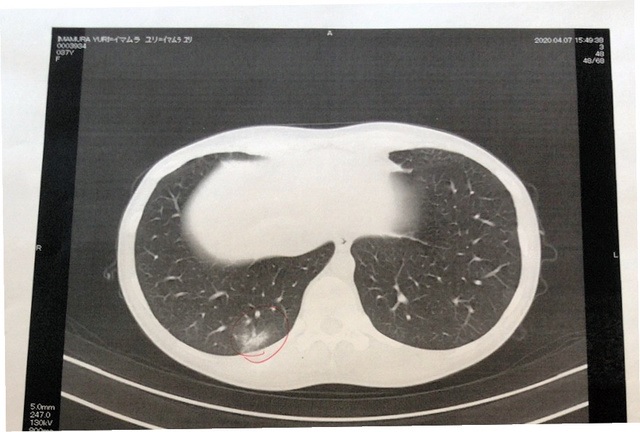

翌日受けたCT検査で、私は軽い肺炎症状が確認されたが、医師は「自然に治るレベル」と話し、特に薬は出なかった。1日4回の検温と、血圧と血中酸素濃度の測定が、毎日の「治療」だった。医師は「この病気に特効薬はありません。しっかり食べて安静にして、体力と免疫をつけてウイルスをやっつけましょう」と語った。

入院した翌日にCT検査を受けた私の肺の画像。赤いボールペンで囲んである部分が右の肺の炎症で、医師は「軽症のなかでも軽症です」と話した